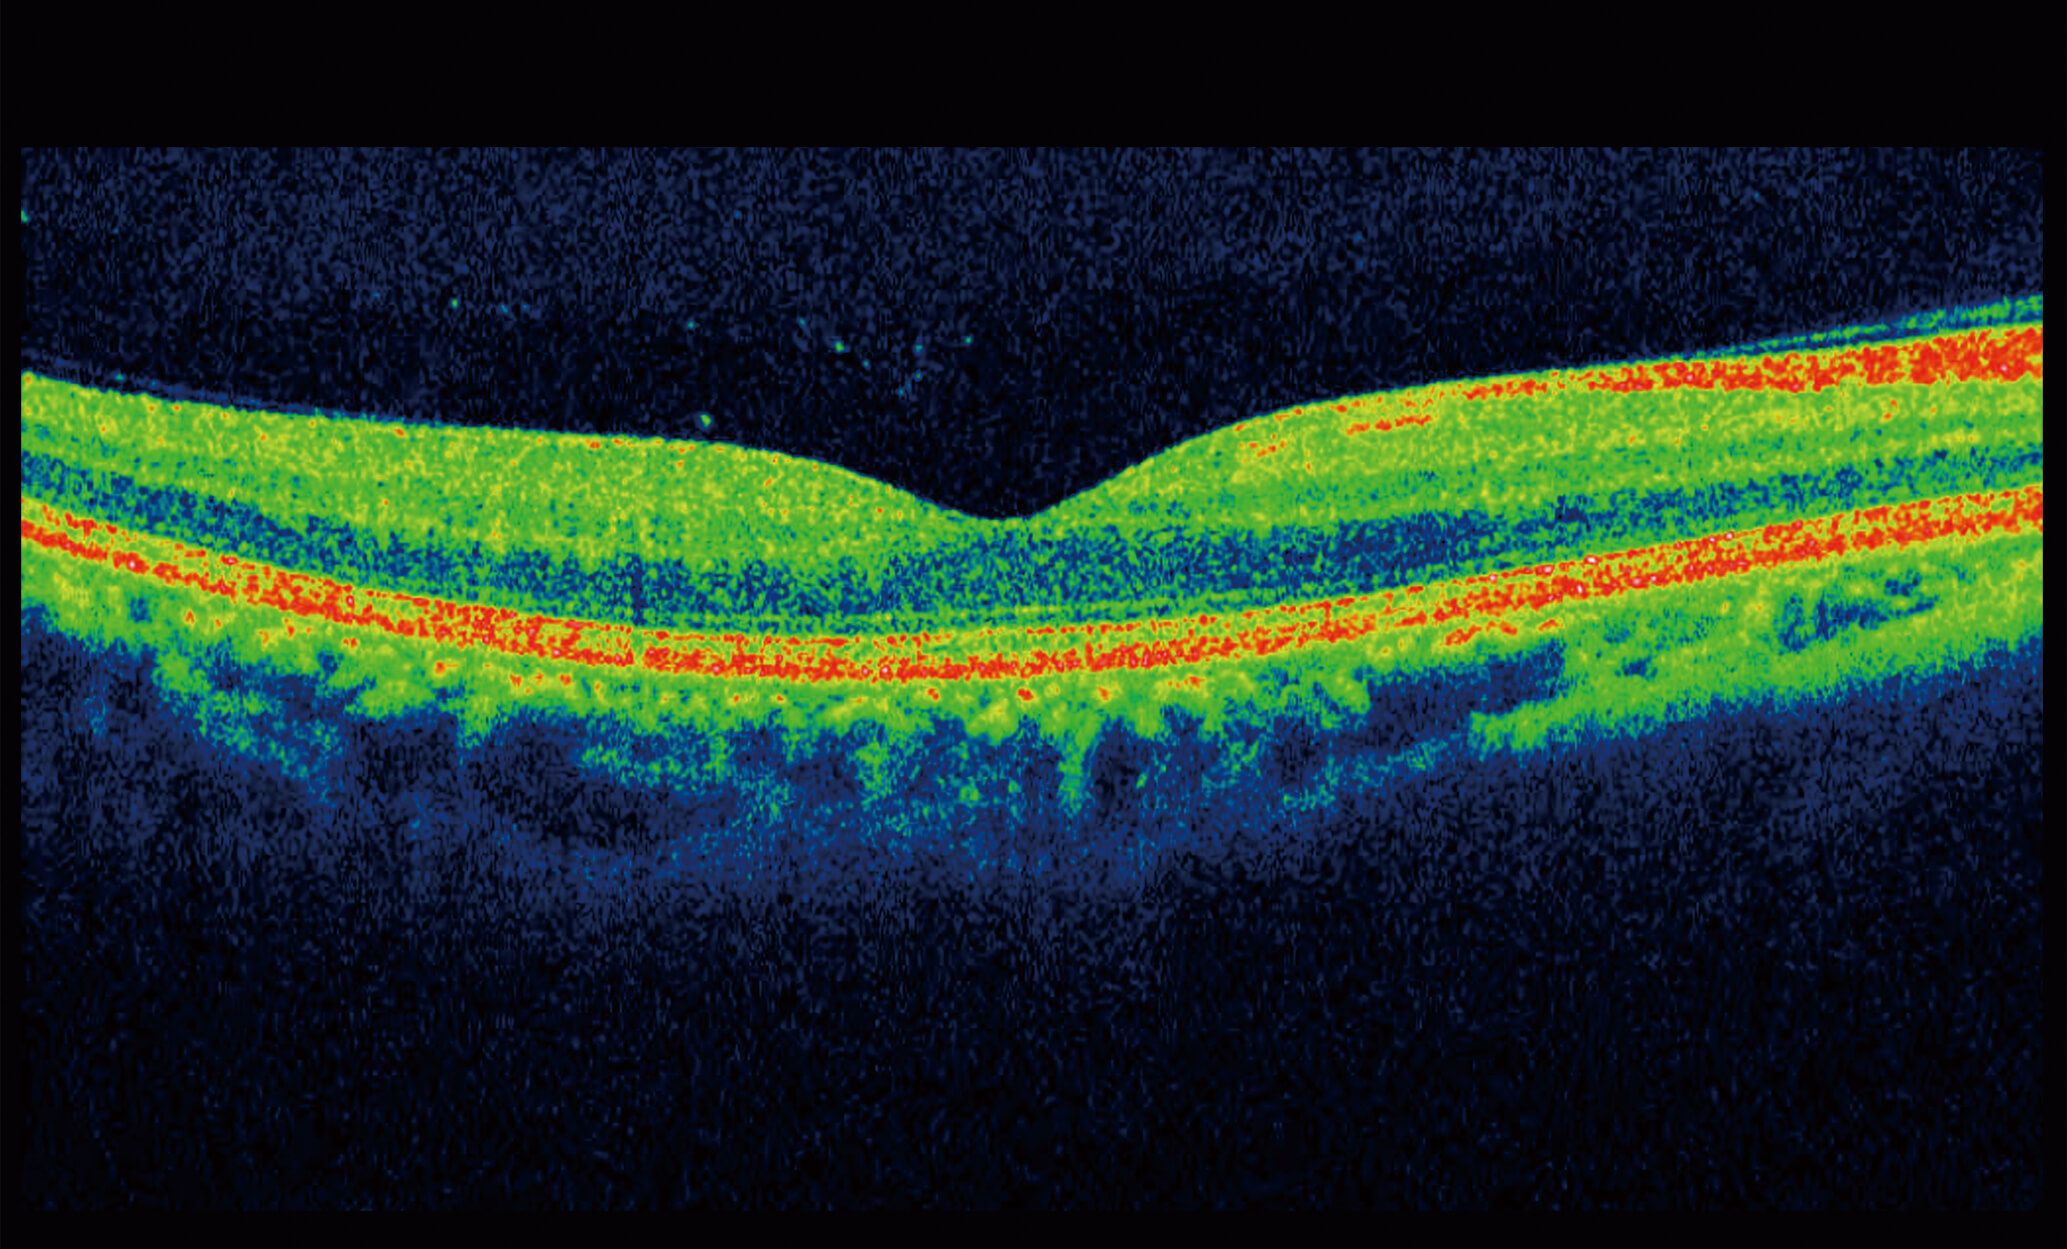

Optical Coherence Tomography (OCT) is an advanced eye scan, similar to ultrasound. The OCT uses light rather than sound waves to illustrate the different layers that make up the back of the eye. Within 2 seconds, the OCT takes over 30,000 individual scans of the back of the eye and this is used to produce a 3D image of the retina and optic nerve. The scan gives an accurate cross-sectional map through the retina and allows examination of the back of the eye in incredibly fine detail.

The OCT also captures a digital photograph of the surface of the eye at the same time, and this can then be cross-referenced with any areas of concern.

The scan shows us beneath the surface of your retina, so we can see and better understand the very fine changes which can be indications of something unhealthy or abnormal.